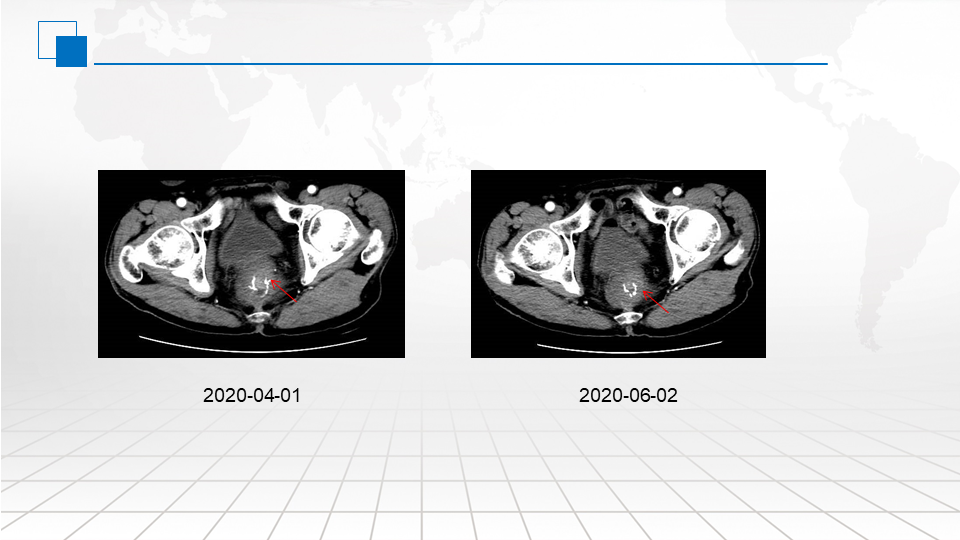

治疗期间,患者肛门坠胀感、疼痛感,小便带血症状明显改善。复查肿瘤标志物CEA持续下降;局部复发肿瘤体积逐步缩小。2020.04.01复查CT评估病情PR。肿瘤标志物CEA已降至正常。

考虑患者经过4月余的全身系统治疗,症状明显改善,肿瘤逐渐缩小,病情稳定,肿瘤标志物基本正常,故患者进行维持治疗阶段。患者后于2020.4.2、2020.4.17、2020.5.3、2020.5.19、2020.06.03、2020.06.19在我科行西妥昔单抗700mg +卡培他滨1.5g bid d1-7, 每2周重复,维持治疗6周期。

治疗期间患者一般情况尚可,CEA维持正常水平。2020.06.02复查CT评估病情SD。